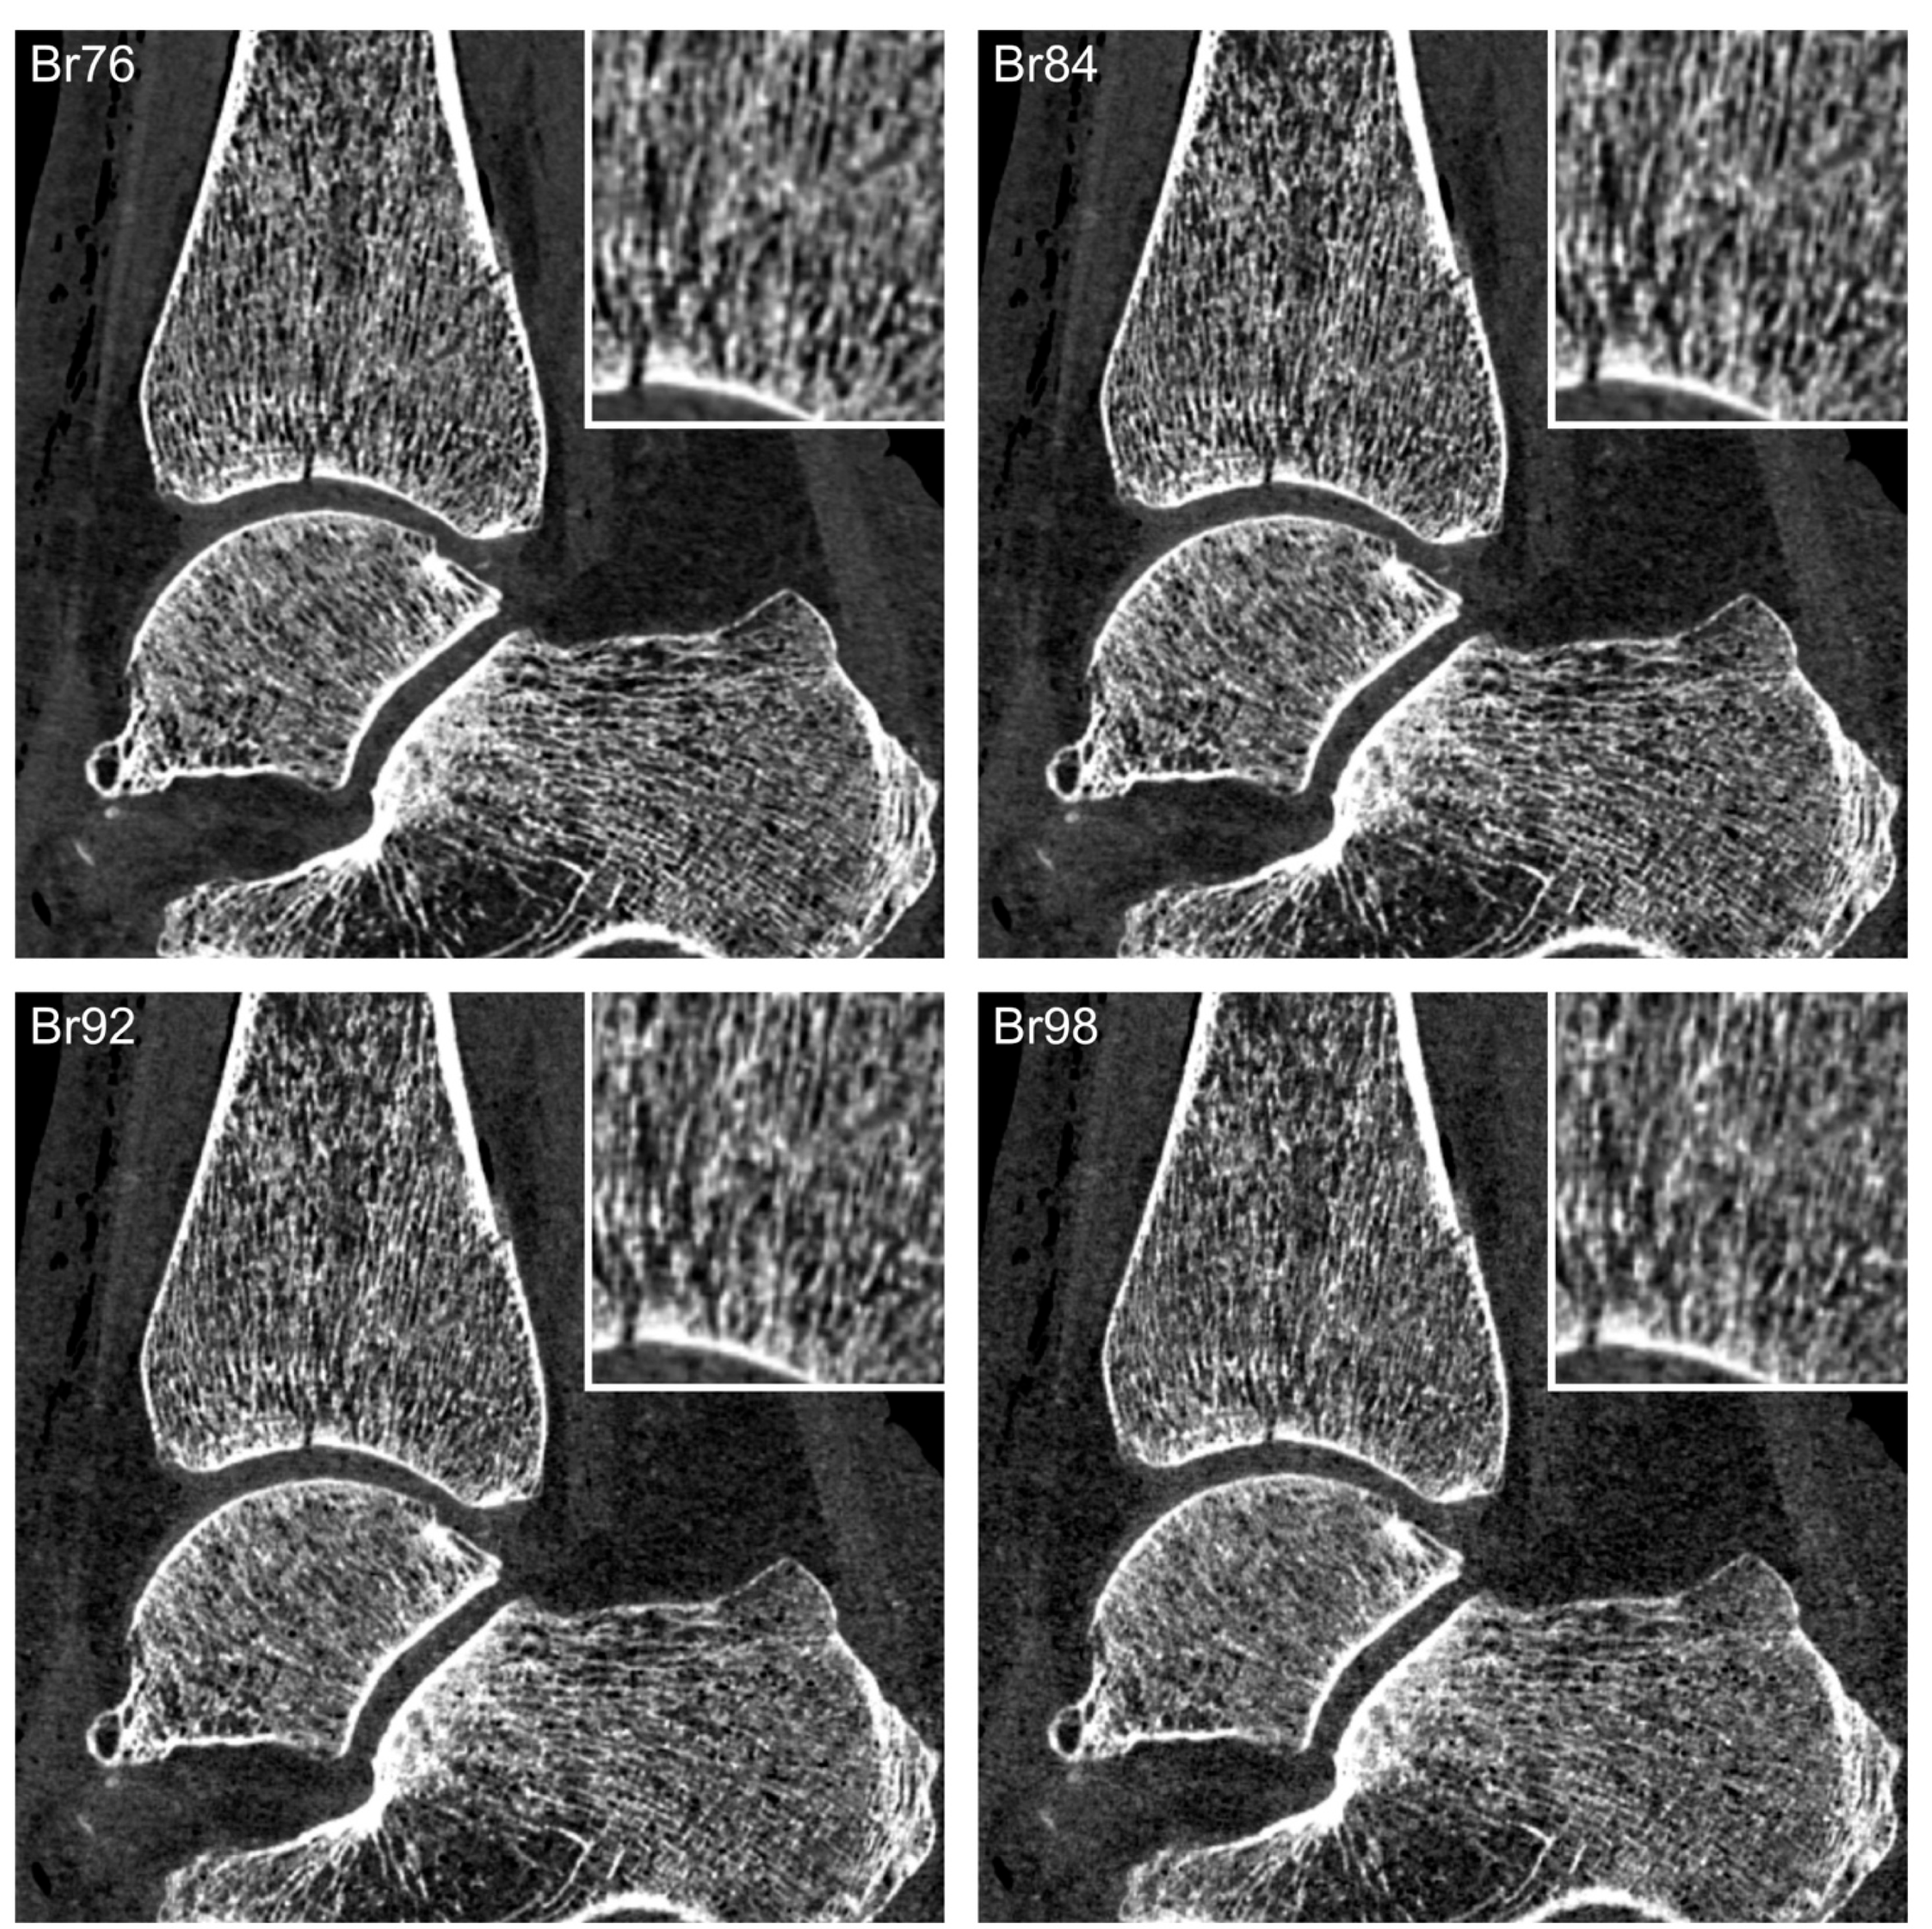

| Br76 | 16.5 | 21.0 | 7.8 |

| Br84 | 22.6 | 27.9 | 10.5 |

| Br92 | 30.4 | 33.5 | 15.1 |

| Br98 | 39.0 | 42.9 | 20.4 |